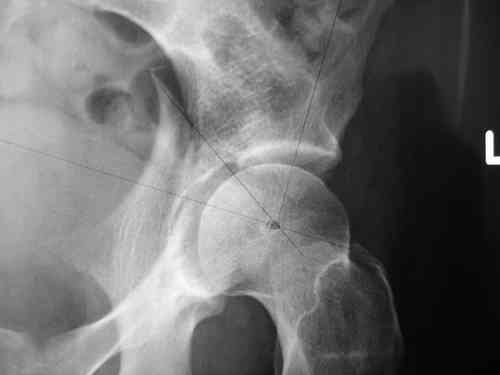

прилагаю пример с такой же давностью травмы, репонировали аппаратом

> R-негативного стола. Зато новый ЭОП. Как вы проводите илиосакральные

> винты? хотябы кратенько методику.

стаскиваете пациента вниз, кладете под ноги какую-нибудь подставку, а дальше как обычно, можно , например, прочитать здесь